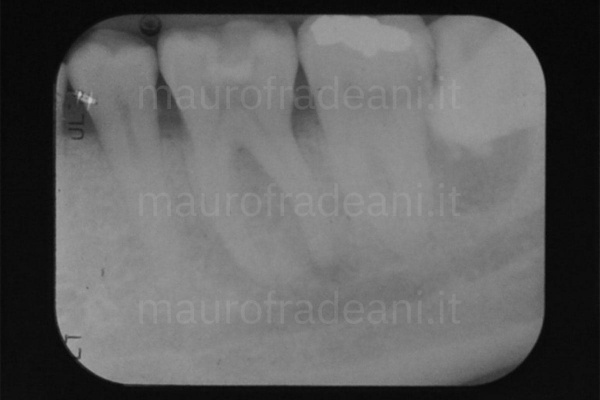

I principali trattamenti quali otturazioni e ricostruzioni, volti a preservare il più possibile la sostanza dentale ripristinando l’integrità dei denti, si effettuano con materiali ad alta valenza estetica: resine composite o ceramica che garantiscono un risultato eccellente e stabile nel tempo.

In tutti questi casi il trattamento endodontico (detto anche terapia canalare o devitalizzazione) è volto a salvare il dente ed evitarne l’estrazione.